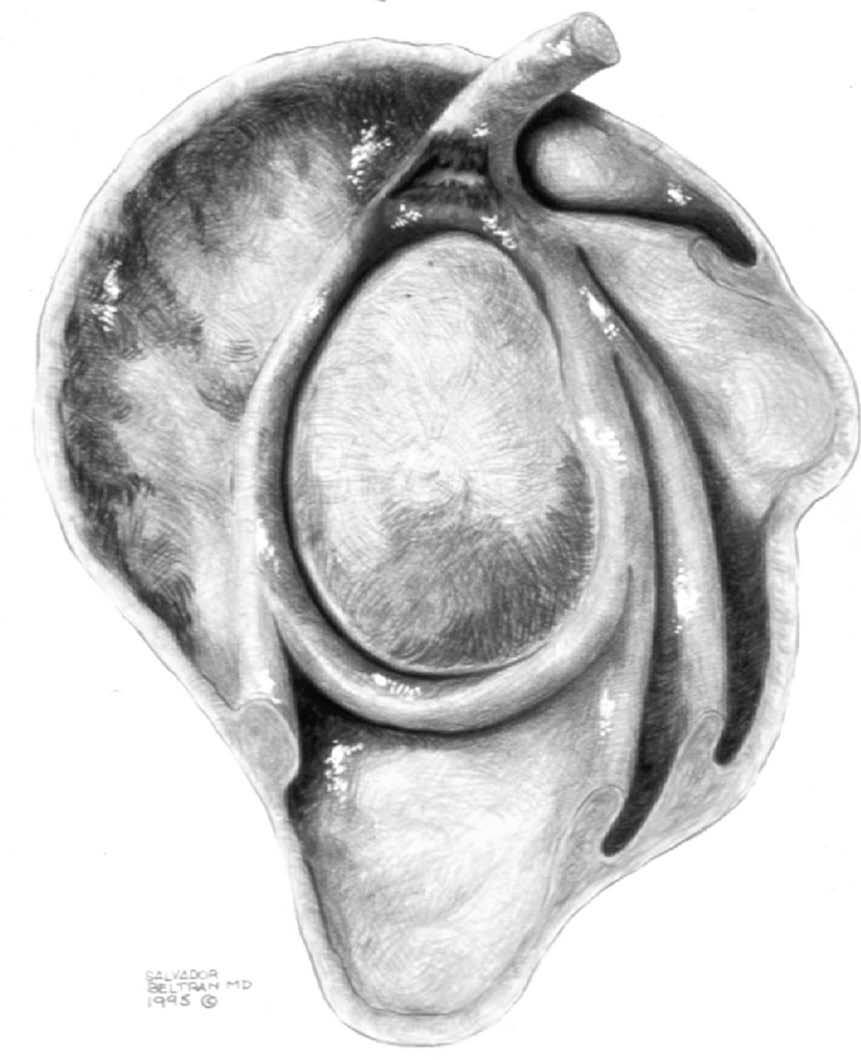

El TLB, LCH y el ligamento coracoacromial (LCA) son también estructuras importantes que contribuyen en diferentes formas a la biomecánica normal del hombro. El LCH ha recibido cierta atención en la literatura reciente y, hoy en día, es considerado una estructura importante junto con el LGHS en la estabilidad del TLB, las lesiones de pinzamiento anterosuperior y en las lesiones del intervalo del MR. La relación anatómica entre estas estructuras (TLB, LCH y el LGHS) es compleja. El punto de origen de cada una de estas estructuras es diferente, pero las tres confluyen en una zona situada, aproximadamente, en el borde superior del troquiter (fig. 6). El TLB se inserta en el borde superior del LG y en el tubérculo bicipital. El LCH se origina en la base de la coracoides y se inserta en el borde superior del troquier por encima y por delante del TLB. El LGHS se origina en el borde superoanterior del LG y se inserta en el borde superior del troquiter, por debajo del TLB.

Fig. 6.--Anatomía del ligamento coracohumeral (LCH), tendón largo del bíceps (TLB) y ligamento glenohumeral superior (LGHS) (polea reflectora). En un corte medial (1) el LCH se halla por encima del TLB y el LGHS por delante. En un corte intermedio (2) el LGHS se halla por delante del TLB. En un corte más lateral (3) el LGHS se encuentra por debajo del TLB.

Lesiones del intervalo del manguito de los rotadores

El intervalo del MR es el espacio más o menos triangular localizado entre el borde anterior del tendón del supraespinoso y el borde superior del tendón subescapular. Este espacio anatómico está cubierto por la cápsula articular y contiene las siguientes estructuras (fig. 31): el LGHS, el LCH, el TLB y el borde anterosuperior del borde glenoideo. Los puntos de origen e inserción de estas estructuras se han descrito anteriormente, sin embargo es de notar que la relación entre el TLB y los LGHS y LCH, cambia a medida que estas tres estructuras se extienden desde sus puntos de origen hasta la zona proximal de la corredera bicipital (fig. 6). A nivel medial, aproximadamente a la altura de la articulación glenohumeral, el LCH se encuentra por encima del TLB y el LGHS se encuentra por delante de ambos. A nivel del troquiter el LGHS se coloca por delante y por debajo del TLB. A nivel de la parte proximal de la corredera bicipital, el LGHS se halla por debajo del TLB, mientras que el LCH permanece por encima del TLB. Esta distribución anatómica provee una estabilidad del TLB durante el movimiento del hombro (polea reflectora).